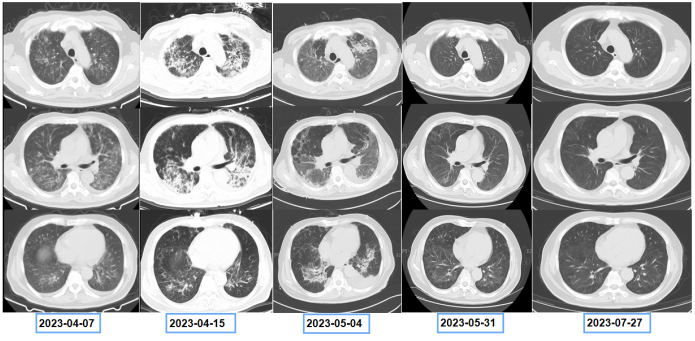

患者既往前列腺癌病史,双肺弥漫间质性病变,考虑肿瘤不能除外,遂于4月15日进一步行PET-CT(图4),结果显示:双肺多发病变,纵隔及双肺门淋巴结代谢增高,考虑炎症。前列腺代谢不均匀增高,符合前列腺癌表现。左侧耻骨及双侧坐骨骨质异常伴代谢增高,考虑转移。患者双肺病变较前快速进展(图5)

图5  患者胸部CT变化